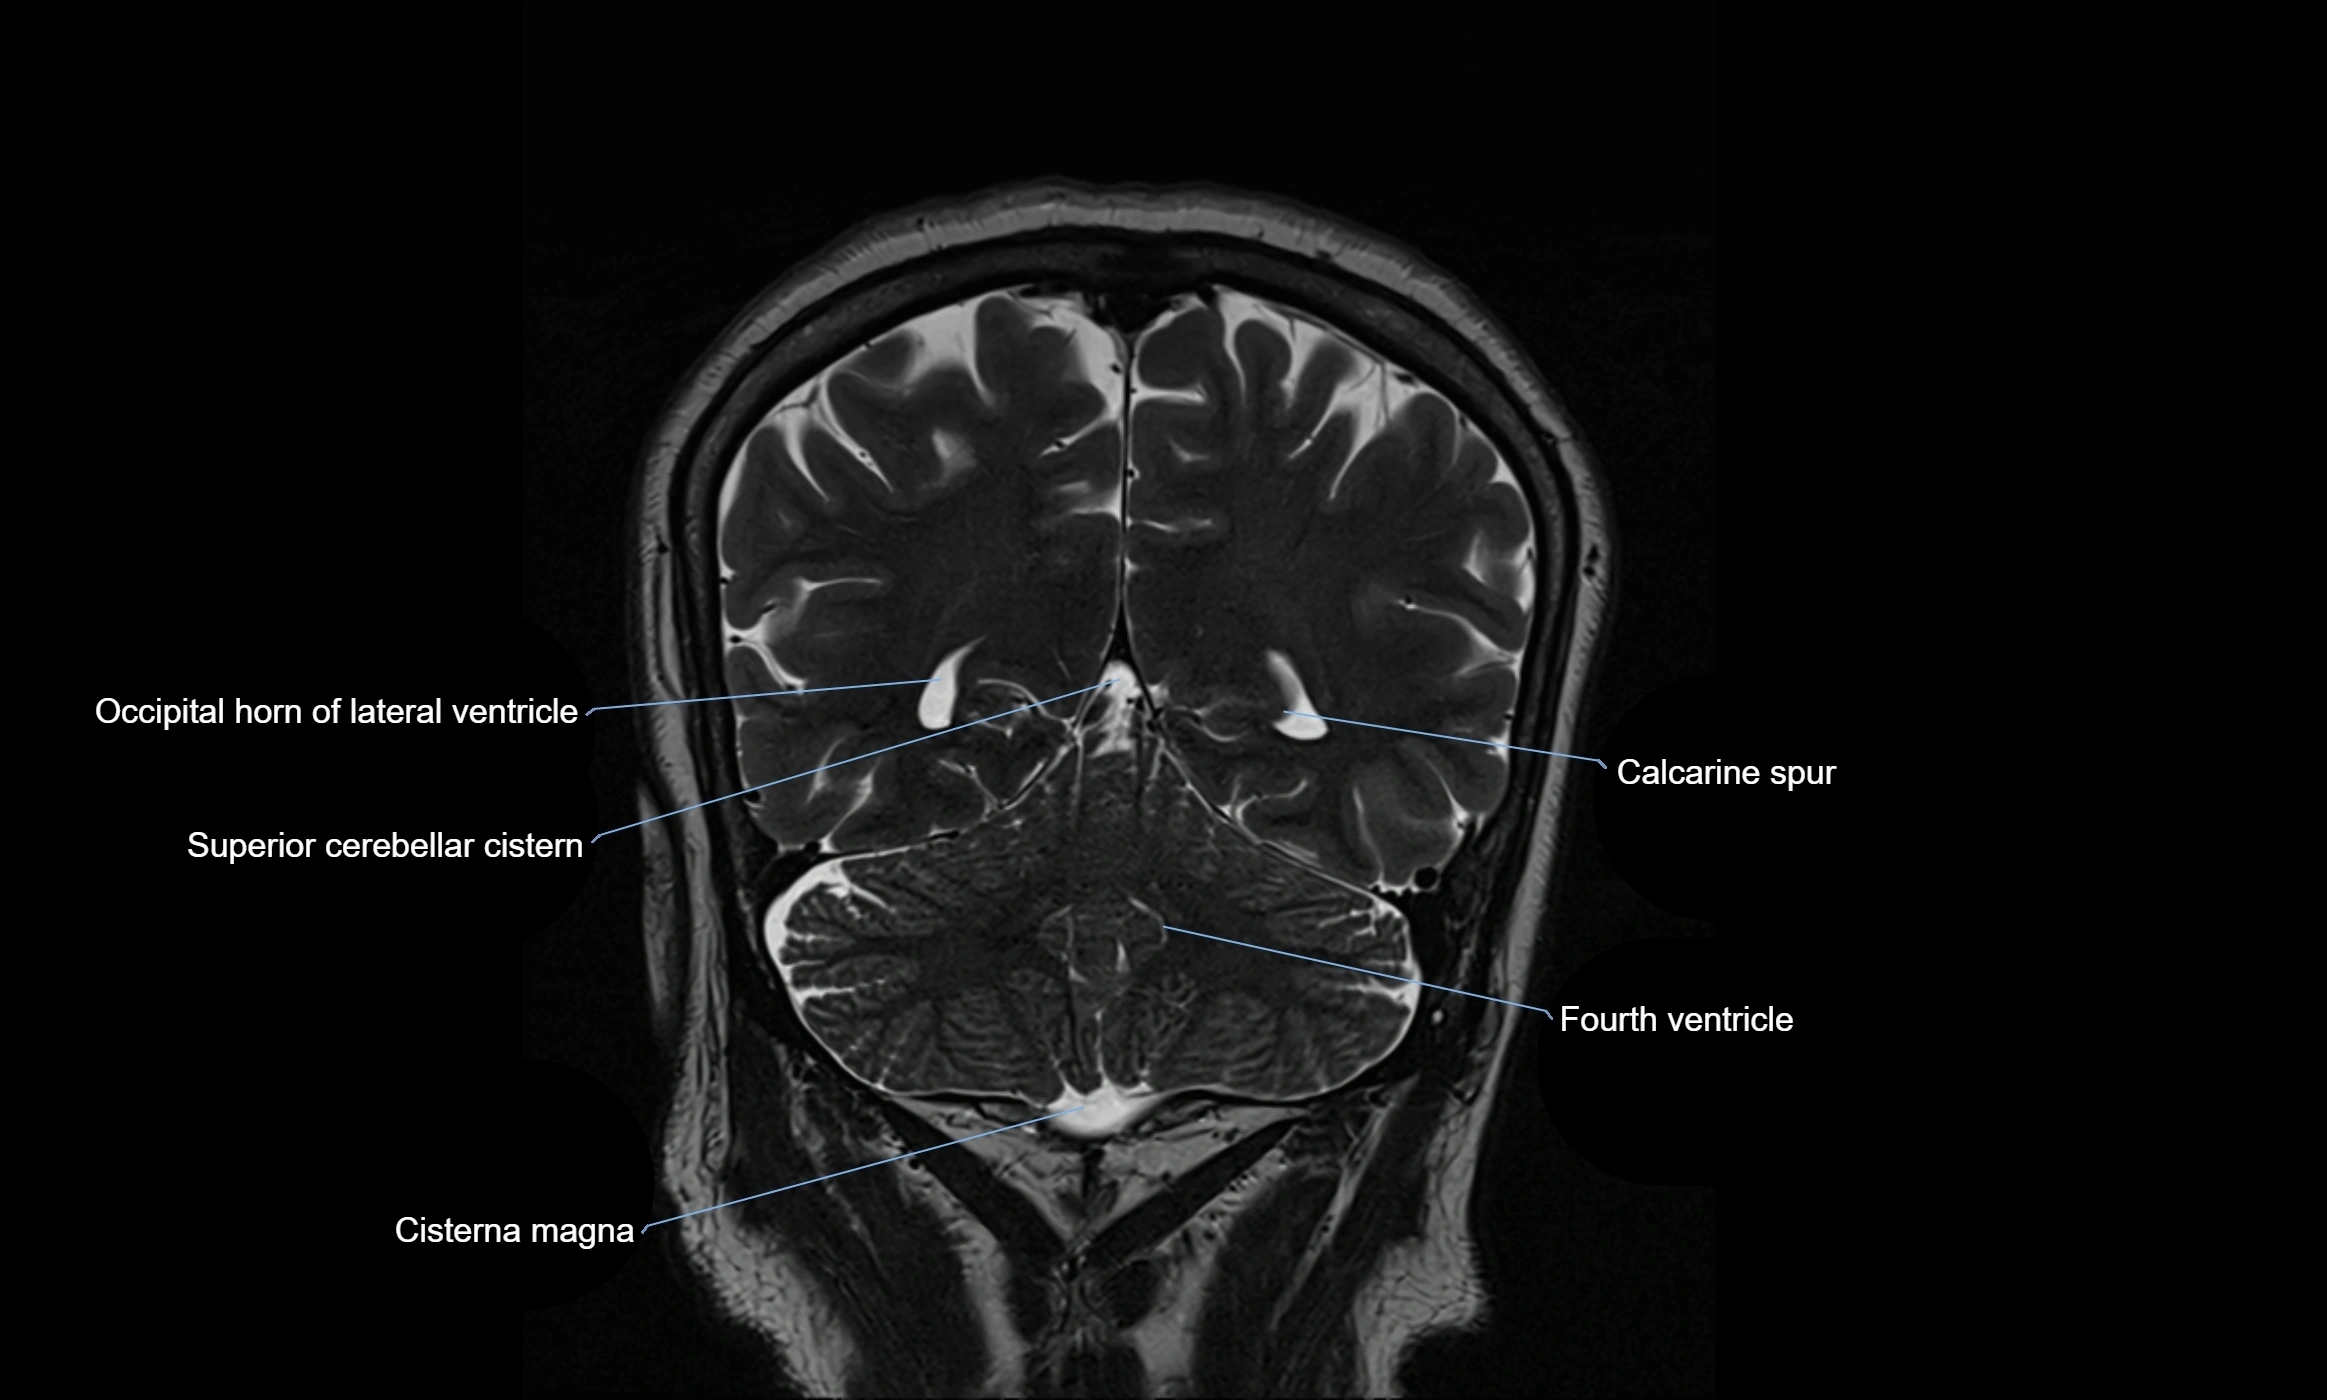

CT image

image